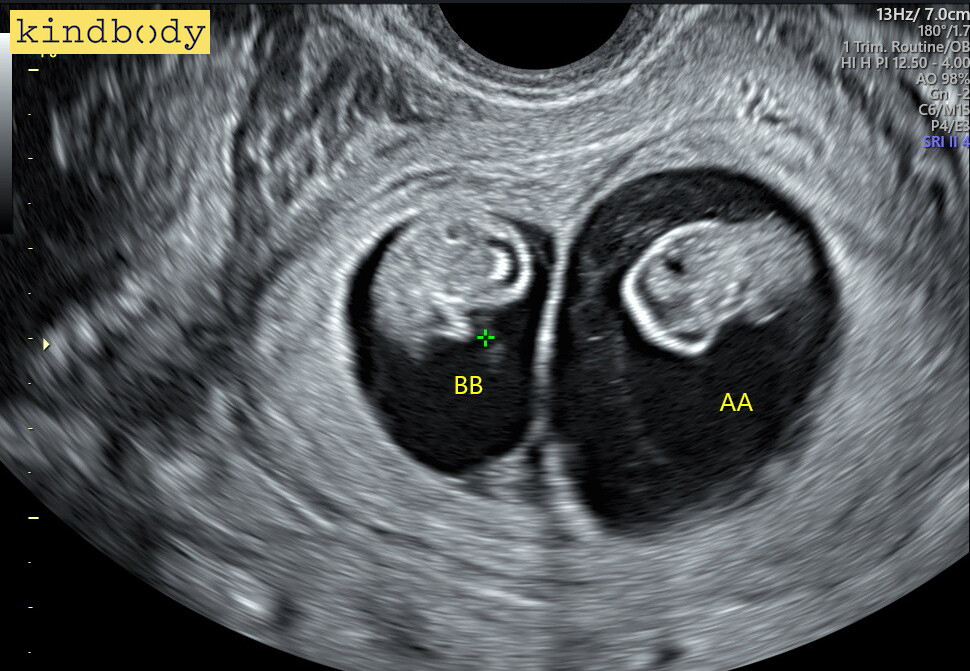

First and foremost, Dr. Cain is an amazing doctor and person. She was our first selling factor for Kindbody. Everyone we met along the way has been great as well. We have recommended everyone we know to Kindbody, resulting in three babies within our friend group. We had a successful pregnancy which resulted in our amazing firstborn Kindbaby. When she was a year old, we started the process again and are now pregnant with twins. Kindbody is and will always be one of the reasons we have grown our family.